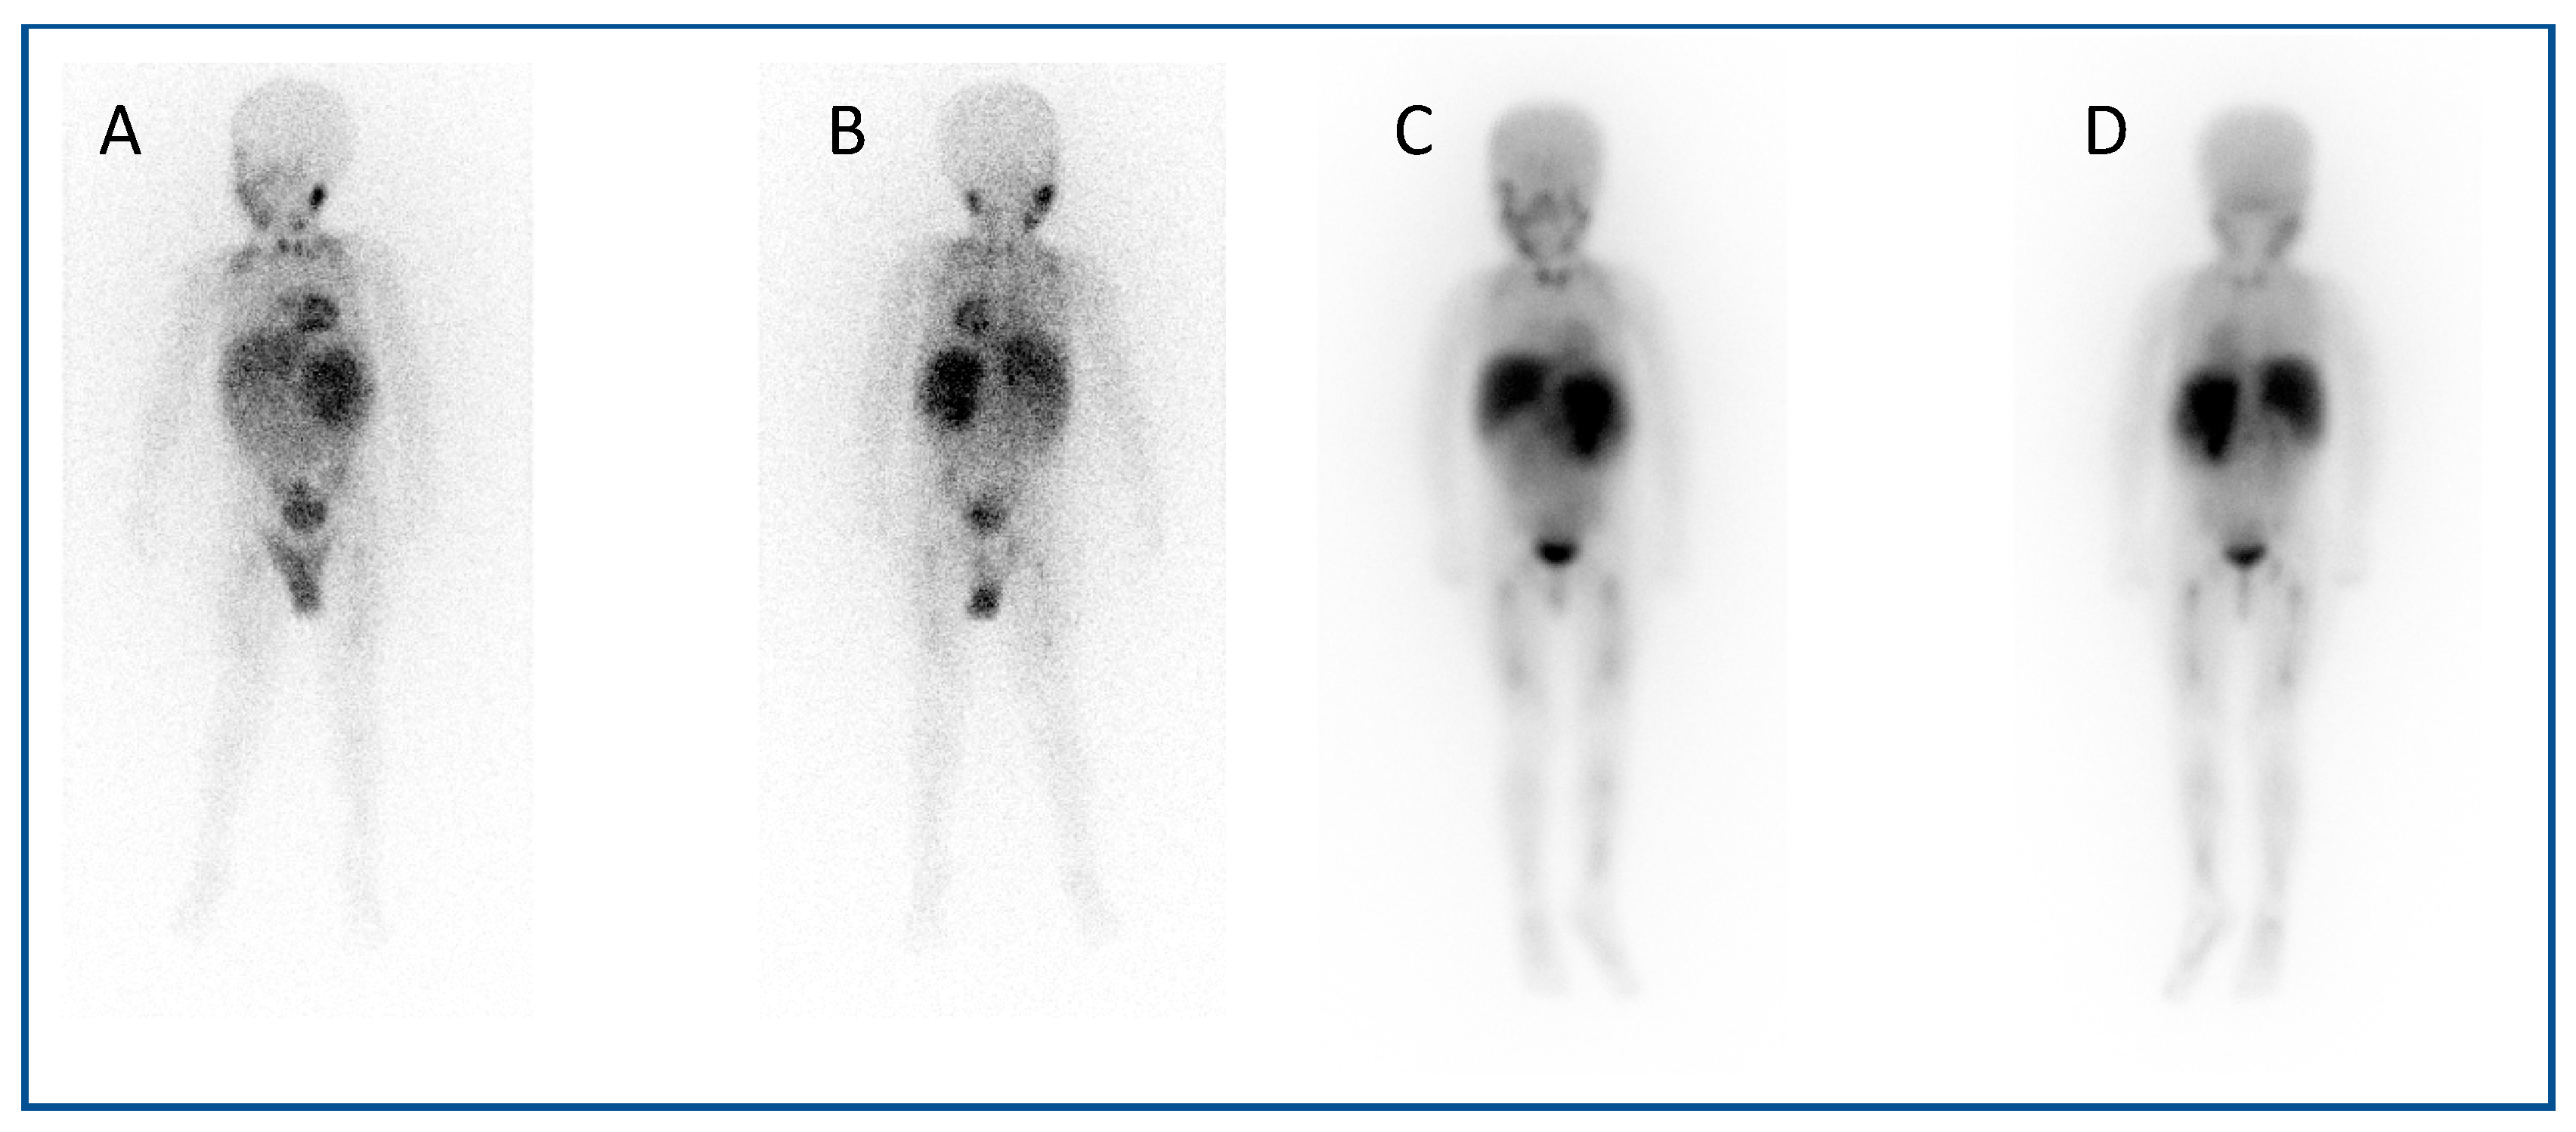

123I mIBG (meta-Iodobenzylguanidine) scintigraphy is the gold standard imaging modality for staging in neuroblastoma (Figure 1A,B), and various semi-quantitative systems have been devised which correlate with prognosis [15,16,17]. Over 90% of patients with neuroblastoma express the noradrenaline transporter molecule and so take up mIBG [18], and scintigraphic demonstration of this is used to select patients for 131I mIBG therapy (Figure 1C,D) [19].

Figure 1.

An example of a theragnostic pairing of radiopharmaceuticals in a child with metastatic neuroblastoma. Diagnostic 123I-mIBG imaging (A) anterior and (B) posterior views of whole-body planar scintigraphy demonstrating pathological uptake in a large left sided retroperitoneal mass as well as in metastatic disease in the femora and jaw, as well as physiological uptake in the salivary glands, heart, liver, urinary bladder and (despite blockade) in the thyroid gland. Corresponding (C) anterior and (D) posterior images following 131I-mIBG therapy administration showing uptake of the agent in the tumour and metastases as well as in physiological sites.